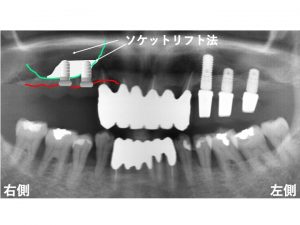

以下の緑線が上顎洞です。

次に

現在の骨を赤線で記載します。

骨の高さが非常に少ないです。

このままであると

本当に短いインプラントしかできません。

以下のようでは、インプラントはきちんとできません。

そこで上顎洞内部に人工骨を入れます。

インプラントを埋入します。

以下が実際のインプラント手術後です。